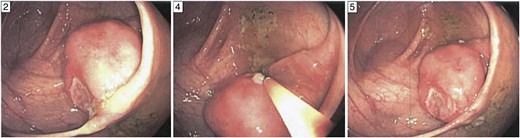

We report a case of a 62-year-old man with a past medical history significant for hypertension and hypothyroidism who underwent diagnostic colonoscopy for melena at an outside facility at ∼9:00 a.m. on the day of the injury. The gastroenterologist identified a large nearly 4 cm pedunculated and ulcerated polyp at the medial border of the cecum in close proximity to the ileocecal junction (Fig. 1). Given the characteristics of the polyp, the concern for malignancy was high. The lesion was removed endoscopically in its entirety through the use of a hot snare.

Ileocecal plasmacytoma. Gross appearance of polyp during the diagnostic colonoscopy for our case. The polyp measured nearly 4 cm and had an obvious ulceration on its surface as shown. It had a thin, long stalk and so was removed by hot snare.